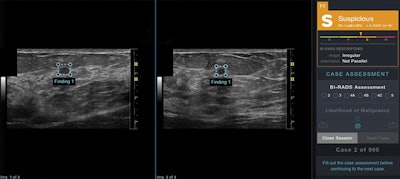

Using version 2.0.0.1 of the Koios DS Study Tool (Koios Medical), the readers analyzed 900 breast lesions twice over two sessions. In the first session, the cases were randomly presented to the readers in one of two ways: as ultrasound images only or as ultrasound images with assistance from the software. In the second session four weeks later, the readers assessed the same cases, but in the opposite format.

"Our study indicates that AI-based [decision-support] output sensitivity and specificity compare favorably with those of interpreting physicians from various subspecialties in the evaluation of static orthogonal breast [ultrasound] images," wrote the researchers, led by first author Dr. Victoria Mango of MSKCC. "Interestingly, the system's stand-alone performance, as measured by AUC, was still higher than [ultrasound] plus [decision support]. Given the performance of the stand-alone system, the [decision-support] output may have a larger impact if it is used more frequently."